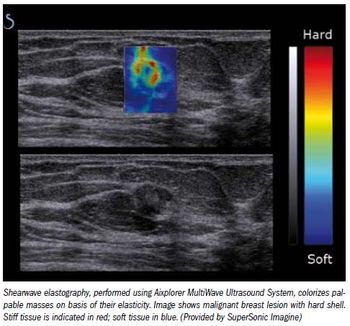

Reducing the number of breast biopsies by better classifying suspicious lesions noninvasively could improve healthcare and cut healthcare costs, laudable goals in the current era of healthcare-and economic-reform.